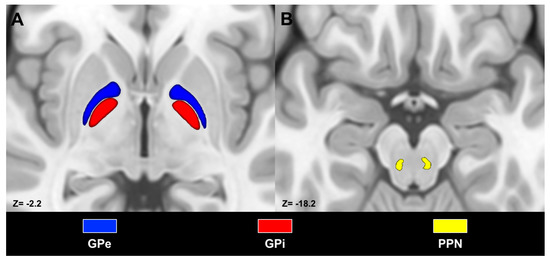

- Bertino, S.; Basile, G.A.; Bramanti, A.; Anastasi, G.P.; Quartarone, A.; Milardi, D.; Cacciola, A. Spatially coherent and topographically organized pathways of the human globus pallidus. Hum. Brain Mapp. 2020. [Google Scholar] [CrossRef]